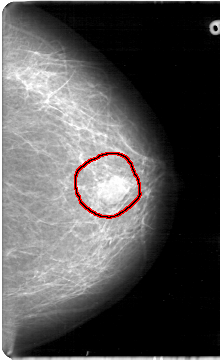

FILE: D_4083_1.LEFT_MLO.OVERLAY

TOTAL_ABNORMALITIES 1

ABNORMALITY 1

LESION_TYPE MASS SHAPE OVAL MARGINS OBSCURED

ASSESSMENT 0

SUBTLETY 5

PATHOLOGY BENIGN

TOTAL_OUTLINES 1

BOUNDARY